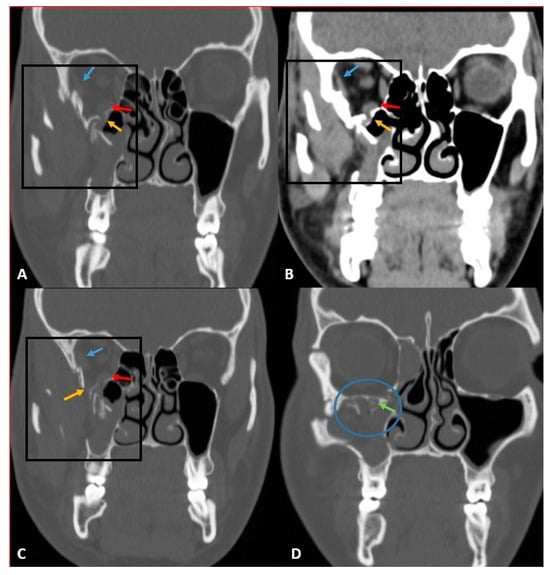

- Betts, A.M.; O’brien, W.T.; Davies, B.W.; Youssef, O.H. A systematic approach to CT evaluation of orbital trauma. Emerg. Radiol. 2014, 21, 511–531. [Google Scholar] [CrossRef] [PubMed]

- Lee, H.-J.; Jilani, M.; Frohman, L.; Baker, S. CT of orbital trauma. Emerg. Radiol. 2004, 10, 168–1672. [Google Scholar] [CrossRef] [PubMed]